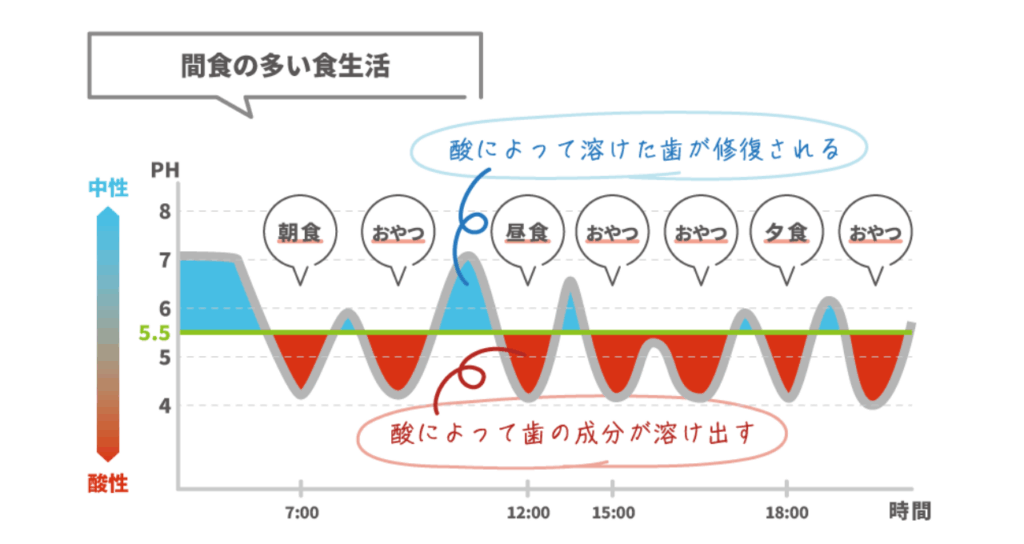

バランスが崩れると虫歯が発生

しかし甘いものを頻繁に摂取したり、歯磨きが不十分であったりすると酸に晒される時間が長くなり、再石灰化による修復が追いつかなくなります。

脱灰が優位な状態が続くことで歯の表面が実質的に溶けて穴が開いてしまう。

これが「虫歯」の始まりです。